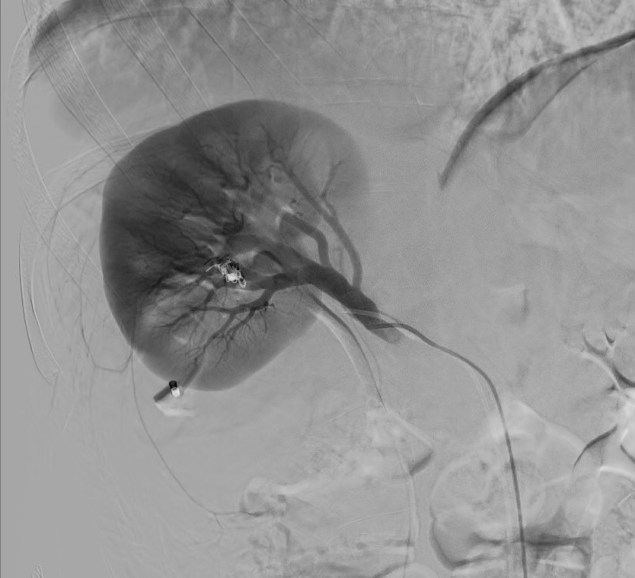

Se realiza Tc con contraste para completar estudio de extensión, en el que se confirman los hallazgos visualizados en la ecografía incluido el nódulo metastásico umbilical (FIGURA 8).

8